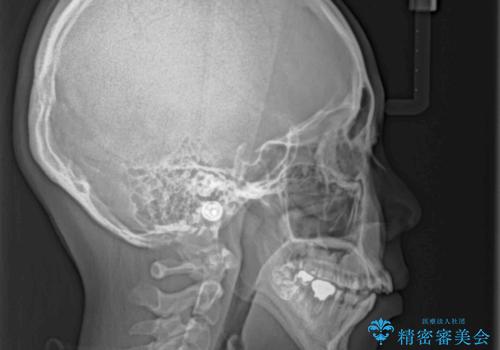

- 口元の突出感と開咬を気にして来院された患者様です。

口元の突出感を改善するため、第一小臼歯を抜歯して口元を引っ込めることとしました。

一般的には上下左右の第一小臼歯4本を抜歯しますが、下顎に対して上顎が前方に位置しているため、まずは上顎小臼歯2本を抜歯し、治療経過を見て下顎小臼歯を抜歯するかどうかを決めていくこととしました。

元々むし歯の処置歯が多く、神経を取り除いている歯が多くありましたが、どうやら右上の前歯と小臼歯は外傷により神経を失った可能性があり、抜歯したスペース前後の歯が全く動かない状態でした。